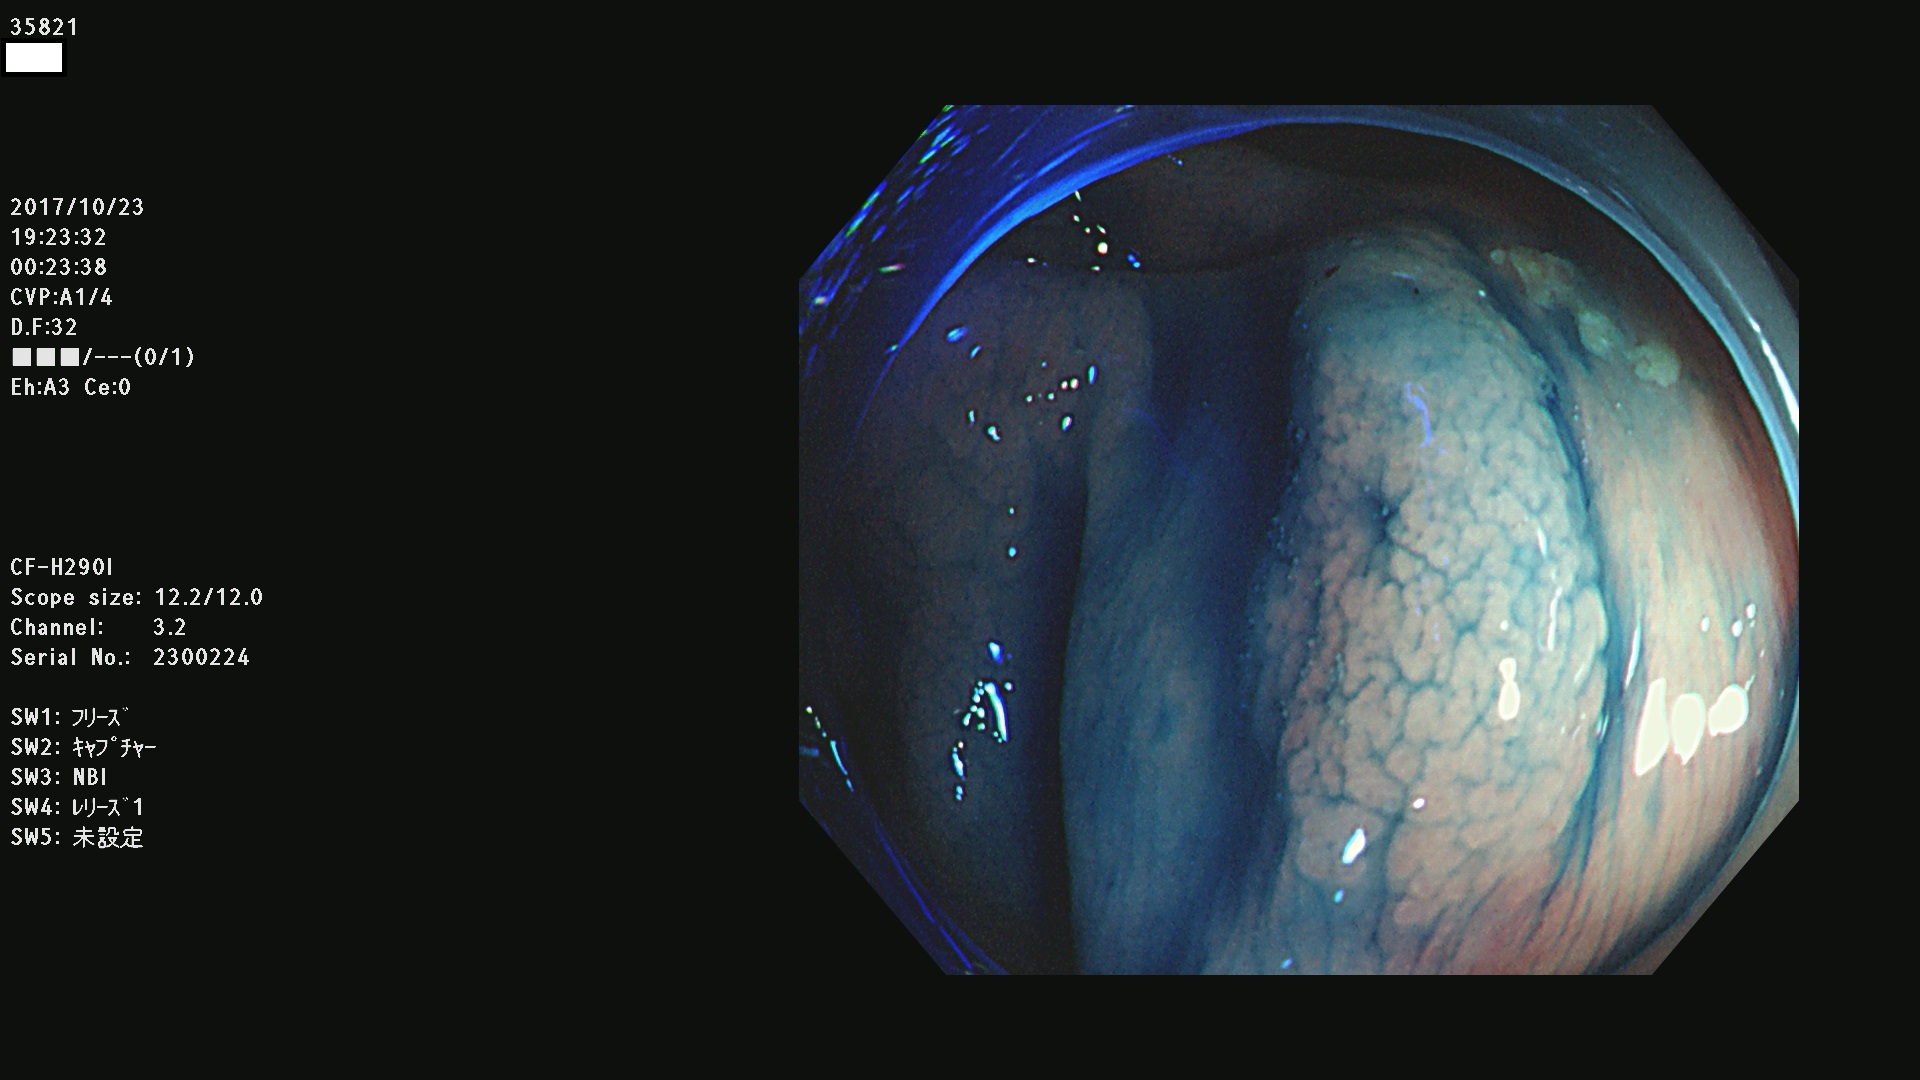

35801 35802 35806 35808 35816 35820 35821 35826 35828 35830(SSA/Pのみ) 35833 35834 35835 35837 35838 35840 35841 35843 35847 35852 35855 35857 35859 35863 35864 35865 35866 35867 35869(SSA/Pのみ) 35872 35873 35875 35878 35880 35882 35885 35886 35888 35890 35893 35895 35896 35897 35898

発見困難で危険性の高い平坦型病変(上記100名より抽出)